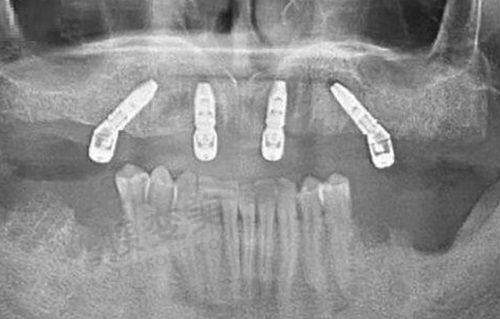

要评价武汉第一口腔医院怎么样,首先得看看它的综合实力。从医院的规模和设施来看,它拥有现代化的诊疗环境,配备了精良的口腔诊疗设备。比如在牙齿矫正方面,精良的设备能够更精细地诊断牙齿问题,为制定个性化的矫正方案提供有力支持。

武汉第一口腔医院在牙齿矫正方面有着显著的技术优势。首先,医院引进了多种精良的矫正技术,如隐形矫正、陶瓷半隐形矫正等。这些技术不仅矫正成效好,而且美观舒适,能够满足不同患者的需求。